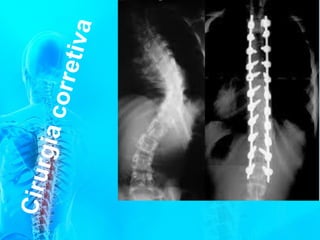

Quando ocorre alguma curvatura neste plano

chamamos de ESCOLIOSE.